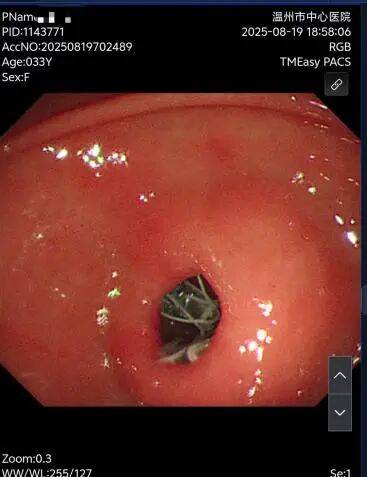

胃流转支架是一种可用于治疗肥胖症的可逆性肠道介入医疗器械。它并非传统意义上的“手术”,而是一项通过内镜(如胃镜)置入的微创治疗手段。医生在无痛胃镜下将特制支架植入胃部或十二指肠区域,改变食物在消化道中的流动路径,模拟部分胃肠道手术的效果,从而实现减重的目标。所以在8月18号经历术前的心电图及心肺功能评估,还有验血项目后,我躺在了内镜中心的手术台上,经历我30多年第一次麻醉内镜手术,在麻醉师给我带上面罩的那一下,我开始睡觉了。

而我在11月25日的时候来取出放置的胃流转支架术,手术过程也是非常的顺利,没有丝毫的痛,等麻醉过后我已经是躺在病床上挂点滴了。